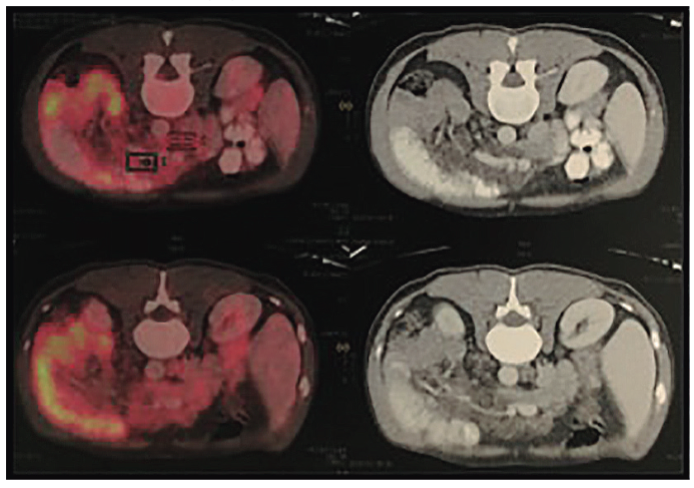

Con base en dichos hallazgos se procede a la realización de una tomografía por emisión de positrones (PET-TC) que evidencia una marcada alteración de la densidad de la grasa intraabdominal asociada a numerosas formaciones ganglionares, algunas de ellas con escasa actividad metabólica con SUV (standardized uptake value) de 3,5 a 6,5 (Figura 1).

Los estudios por imágenes (ecografía, tomografía axial computada, resonancia magnética nuclear) son útiles para descartar otras entidades. La presencia de adenomegalias intestinales en la tomografía con escasa actividad metabólica en el PET-TC orientó hacia un cuadro infeccioso y alejó la patología neoplásica y linfoproliferativa, en el caso comunicado.